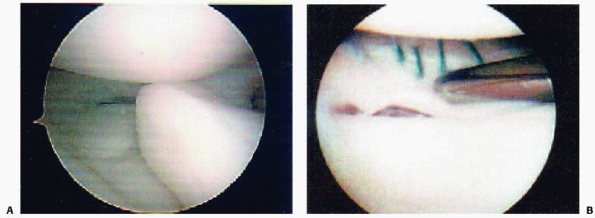

series of 80 skeletally immature patients who underwent surgical

fixation of tibial eminence fractures, Kocher et al.177 found no associated chondral injuries and associated meniscal tear in only 3.8% (3/80) of patients (Fig. 24-1). Associated collateral ligament injury

or proximal ACL avulsion are uncommon, but have been reported.131,252

![]() |

|

FIGURE 24-1 Longitudinal meniscus tear associated with tibial eminence fracture.

displaced tibial eminence fragment has been reported and may be a

rationale for considering arthroscopic or open reduction in displaced

tibial spine fractures (Fig. 24-5).54,59,94,177

Meniscal entrapment prevents anatomic reduction of the tibial spine

fragment, which may result in increased anterior laxity or a block to

extension.120,148,211,236,240 Furthermore, meniscal entrapment itself may cause knee pain after fracture healing.59 Falstie-Jensen and Sondergard Petersen,94 Burstein and colleagues,54 and Chandler and Miller59

have all reported cases of meniscal incarceration blocking reduction of

type 2 or 3 tibial spine fractures in children. The prevalence of

meniscal entrapment in tibial spine fractures may be common for

displaced fractures. As aforementioned, the anterior horn of the

lateral meniscus typically remains attached to the tibial eminence

fracture fragment. However, the anterior horn of the medial meniscus or

the intermeniscal ligament may become incarcerated. Mah and colleagues200

found medial meniscal entrapment preventing reduction in 8 of 10

children with type 3 fractures undergoing arthroscopic management. In a

consecutive series of 80 skeletally immature patients who underwent

surgical fixation of hinged or displaced tibial eminence fractures

which did not reduce in extension, Kocher et al.177

found entrapment of the anterior horn medial meniscus (n = 36),

intermeniscal ligament (n = 6), or anterior horn lateral meniscus (n =

1) in 26% (6/23) of hinged (type 2) fractures and 65% (37/57) of

displaced (type 3) fractures. The entrapped meniscus can typically be

extracted with an arthroscopic probe and retracted with a retaining

suture (Fig. 24-6).